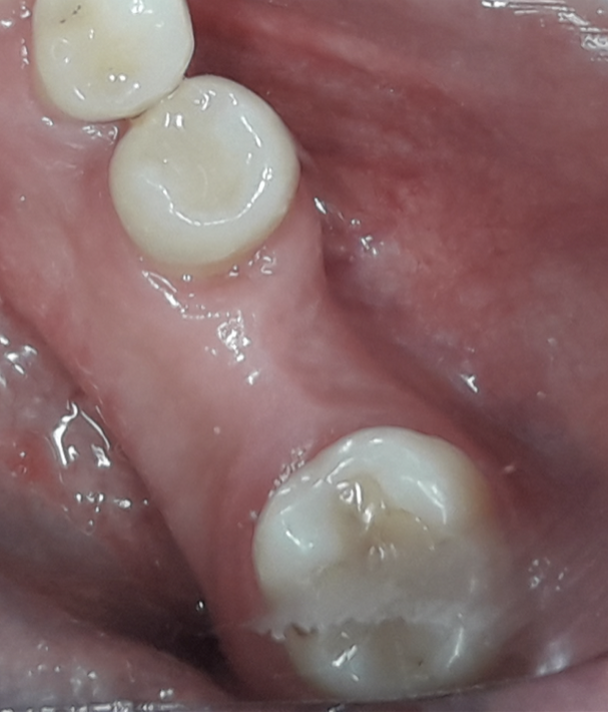

Nello studio sono stati inclusi 20 pazienti (12 donne e 8 uomini) di età compresa tra i 28 e i 65 anni, con edentulia singola e conseguente deficit vestibolare dei tessuti molli. La matrice dermica a elevata consistenza è stata opportunamente ritagliata mediante forbici e lama ed è stata posizionata al di sotto del lembo muco periostale allestito con approccio a spessore totale, vestibolarmente alla cresta ossea in cui è stato posizionato contestualmente un impianto endosseo osteointegrabile. Non si è utilizzato alcun ausilio di fissazione per la matrice dermica che è stata stabilizzata dal solo lembo di accesso ribaltato su di essa e suturato, mediante punti staccati semplici, al lembo linguale.

Le rilevazioni eseguite a distanza di 18 mesi di tempo medio, hanno mostrato un netto miglioramento del PES (Pink Esthetic Score) con un punteggio medio superiore a 9 (eccellente) e in due casi un punteggio tra 6 e 8 (buono). La sovrapposizione dei file .stl provenienti dalla scansione della arcata dentaria interessata prima dell’intervento e a distanza di 18 mesi ha permesso di rilevare un incremento medio in senso orizzontale di 2 mm in media.